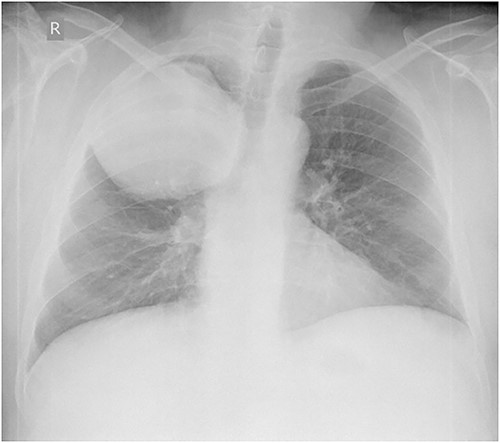

Laboratory tests revealed leukocytosis –10.46 (*10^9/l) with 69.2% of neutrophils, but C-reactive protein was normal (1.37 mg/l). Chest X-ray showed a giant, homogeneous, clearly circumscribed opacity in the upper lobe of the right lung (Fig. 1).

Anteroposterior chest X-ray. Giant, homogeneous, clearly circumscribed opacity in the upper part of the right chest.